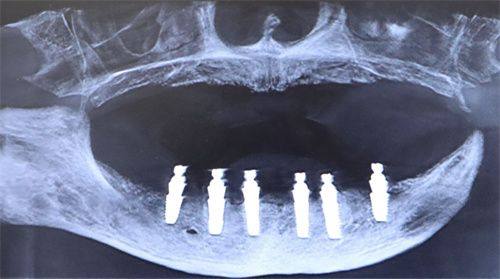

口腔健康状况对种植牙寿命的影响

自身的口腔健康状况也会影响牙齿种植能用多久。如果本身患有牙周病、龋齿等口腔疾病,种植牙的使用寿命可能会受到影响。牙周病会导致牙龈萎缩、牙槽骨吸收,从而使种植牙失去稳定的支撑;龋齿则可能引发牙齿疼痛、感染等问题,波及种植牙。所以,在进行牙齿种植前,更好先治疗好现有的口腔疾病。在种植牙使用过程中,也要定期到牙医处检查,及时发现和治疗新出现的口腔问题。